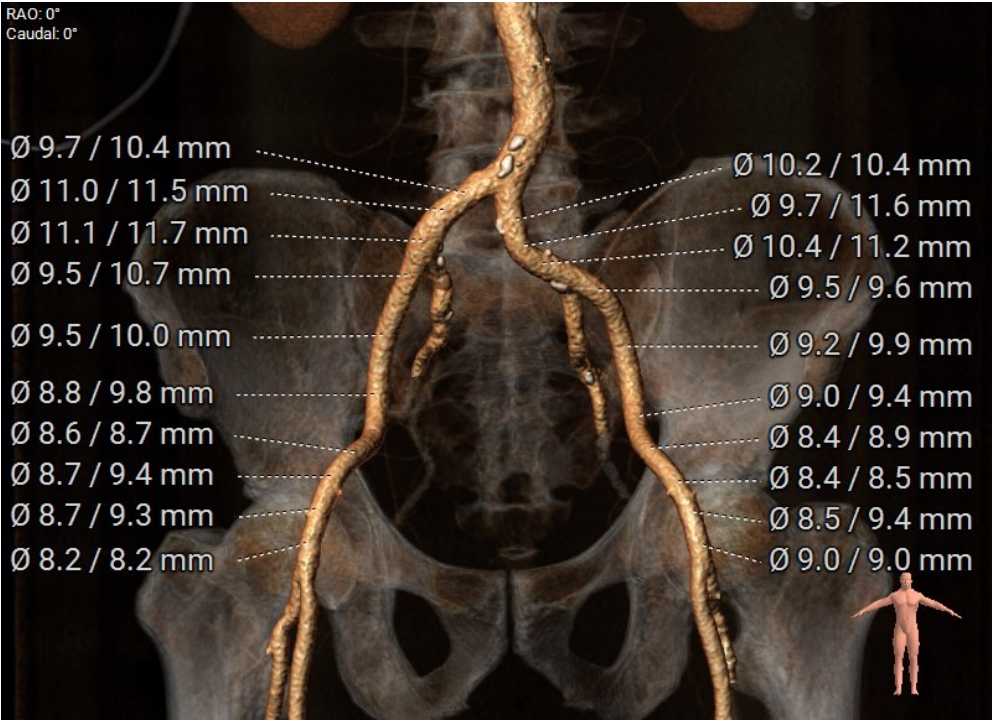

CT分析:

术前CT分析判断该心耳为反鸡翅型左心耳,选择偏下略偏前的位置进行房间隔穿刺。在工作体位造影后,可见左心耳内梳状肌发达,反鸡翅叶显影清晰,鞘管轴向佳。经DSA测量左心耳开口18mm深度17mm,结合TEE测量数据,综合考虑选用WATCHMAN24mm封堵器进行封堵。在展开封堵器时利用在体内借深度技巧,保证封堵器封堵位置合理。封堵器展开后经造影检查封堵器封堵效果理想,牵拉试验稳定。超声评估封堵器各角度无残余分流,位置理想,满足PASS原则,随即释放封堵器,一站式手术顺利结束。